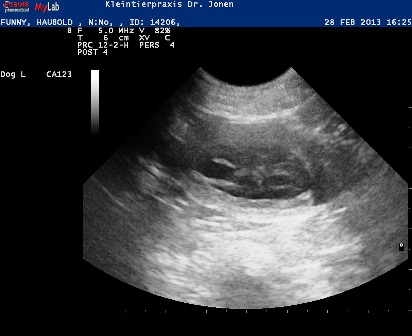

28.02.2013

Heute waren wir beim Ultraschall und Funny ist tragend !!!

Um den 6. April 2013 herum wird unser C-Wurf das Licht der Welt erblicken.